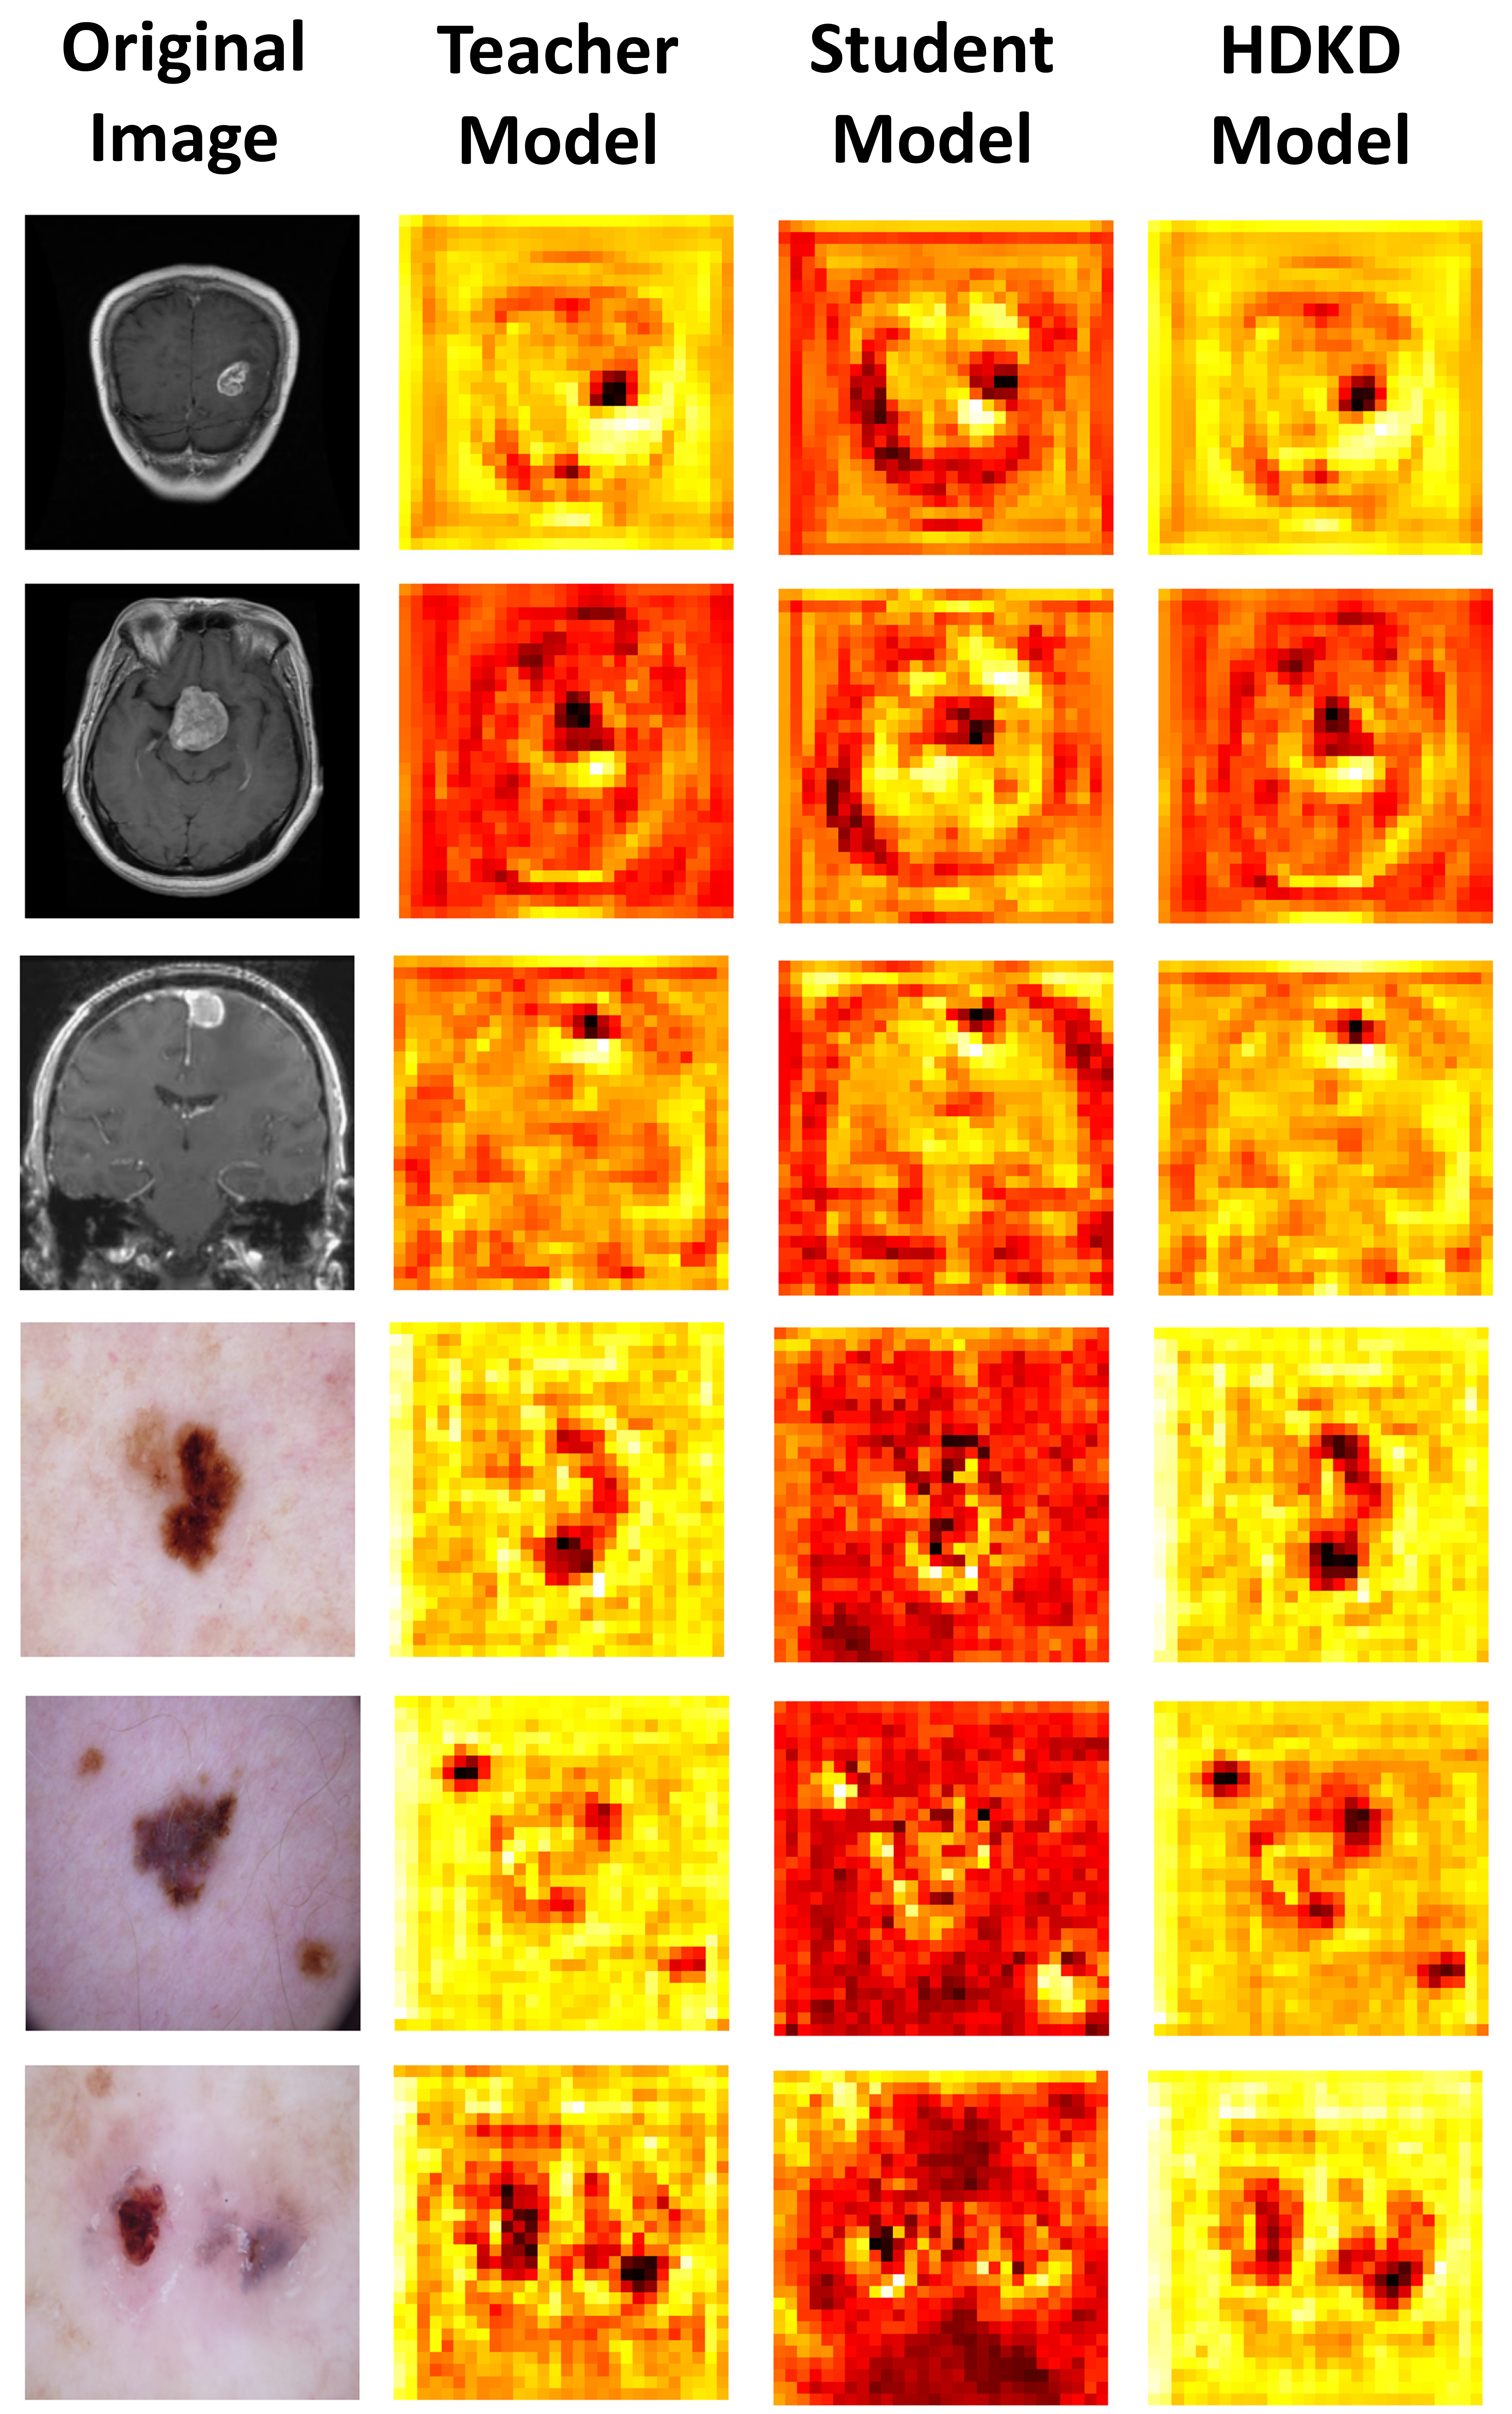

Feature visualization analysis. To explore how distillation impacts HDKD activation maps, we provide visual comparisons of the activation maps generated at the third stage for our three models: the teacher model, the student model without distillation, and the HDKD model. The visual comparison shown in Figure 5. reveals that the HDKD model’s activation maps effectively highlight infection areas more than those of the teacher model and the student model without distillation. Moreover, due to feature distillation, the activation maps of the HDKD model closely resemble those of the teacher model, but with enhanced detail. This demonstrates the HDKD model’s superior ability to capture salient features and its ability to generalize across various tasks.

Refer to caption

Figure 5: Feature visualization analysis. We visualize the activation maps of the last block in the final convolutional stage (3rd stage) for each of the teacher model, student model without distillation, and HDKD model. These activation maps are obtained by averaging across the channel dimension, resulting in a single global channel of size 28×\times×28.